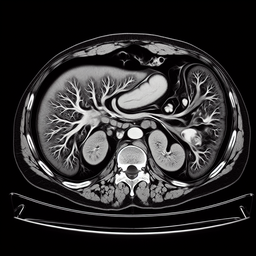

Магнітно-резонансна томографія (МРТ) підшлункової залози — це неінвазивний діагностичний метод, який дозволяє отримати детальне зображення цього органу. Процедура допомагає виявити захворювання, оцінити стан підшлункової залози та навколишніх структур.

- **Комплексна оцінка**: Дозволяє оцінити не тільки підшлункову залозу, але й навколишні органи та судини.